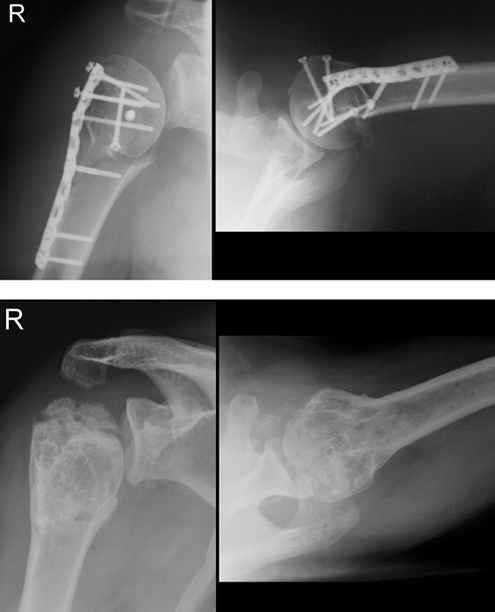

Рис. 31-11. из Rockwood & Green "Fractures in adults" (2006).

А еще хотелось бы увидеть современный стабильный остеосинтез пластинами LPHP, PHILOS, S3 и как его осложнение - асептический некроз..